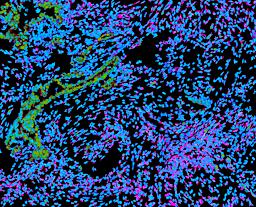

Pancreatic ductal adenocarcinoma is a lethal disease with limited treatment options and poor survival. We studied 83 spatial samples from 31 patients (11 treatment-naïve and 20 treated) using single-cell/nucleus RNA sequencing, bulk-proteogenomics, spatial transcriptomics and cellular imaging. Subpopulations of tumor cells exhibited signatures of proliferation, KRAS signaling, cell stress and epithelial-to-mesenchymal transition. Mapping mutations and copy number events distinguished tumor populations from normal and transitional cells, including acinar-to-ductal metaplasia and pancreatic intraepithelial neoplasia. Pathology-assisted deconvolution of spatial transcriptomic data identified tumor and transitional subpopulations with distinct histological features. We showed coordinated expression of TIGIT in exhausted and regulatory T cells and Nectin in tumor cells. Chemo-resistant samples contain a threefold enrichment of inflammatory cancer-associated fibroblasts that upregulate metallothioneins. Our study reveals a deeper understanding of the intricate substructure of pancreatic ductal adenocarcinoma tumors that could help improve therapy for patients with this disease.